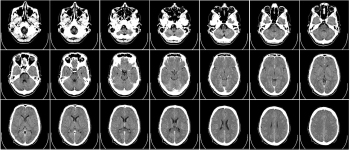

Дослідники з Університету Північної Кароліни в одному з перших досліджень такого роду виявили, що звичка перевіряти соціальні мережі може змінити те, як підлітки в ранньому віці сприймають соціальні заохочення та покарання — зміни досить конкретні, щоб їх можна було розглядати як певні й відмінні нервові шляхи при скануванні мозку.

У статті, опублікованій у Журналі Американської медичної асоціації педіатрії, виявлено значні зміни в мигдалеподібному тілі, ділянці сірої речовини мозку, пов'язаній з пам'яттю та емоціями, у мозку 169 учасників дослідження підлітків із сільської місцевості на Півночі. Середня школа Кароліни.

Учні середніх класів, яким на момент початку дослідження було близько 12 років, самі повідомили, як часто вони перевіряли соціальні мережі на день. Щороку дослідники також проводили сканування мозку, тоді як молоді люди грали у відеогру, в якій перевірялося, наскільки швидко вони можуть ідентифікувати позитивні та негативні соціальні сигнали у вигляді щасливих чи сердитих осіб.